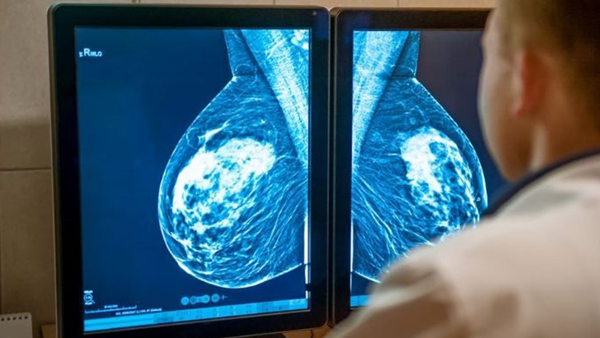

乳腺癌患者的3D打印

女性是患乳腺癌的主要危险因素。尽管男性也会受到影响(每年约占病例的1%),但到2022年,乳腺癌仍然是女性中最常见的癌症。据世界卫生组织称,平均有十二分之一的女性一生中会患乳腺癌,与工业化地区相比,发展中国家的死亡率更高。2022年,全球有230万名女性被确诊,67万人死亡。乳腺癌的特点是异常细胞不受控制地增殖,如果不及时治疗就会扩散。

因此,早期发现和有关可用治疗方法的信息对于减少这些数字至关重要。这就是为什么10月被指定为乳腺癌宣传月,10月19日是世界乳腺癌日。在此期间,世界各地的意识、预防和治疗举措不断增加。此外,越来越多的公司和研究机构正在致力于新技术的开发,以改善对患有这种癌症的女性的护理,包括使用3D打印。以下是一些当前3D打印应用于乳腺癌治疗的项目示例。